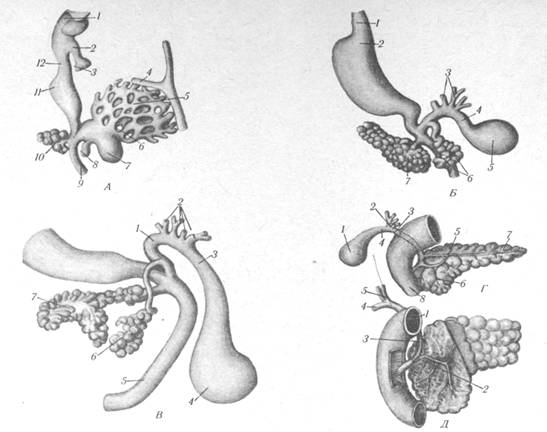

Крупные железы пищеварительного аппарата являются производным эпителия слизистой оболочки первичной средней кишки. Уже на ранних стадиях эмбриогенеза они вынесены далеко за пределы пищевого канала. У четырехнедельного эмбриона человека в слизистой оболочке того отдела первичной кишки, из которого развивается двенадцатиперстная кишка, возникают два клеточных дивертикула. Один появляется на медиальной стенке кишки в виде двойного зачатка (вентрального и дорсального), который вскоре сливается и растет между листками дорсальной брыжейки. Этот зачаток является закладкой поджелудочной железы. Второй клеточный дивертикул возникает на задней стенке кишки, направляется краниально и вправо между листками вентральной брыжейки. Из него развивается печень (рис. 1.1).

Рис. 1.1. Развитие печени и поджелудочной железы:

A. 1 — глотка; 2 — трахея; 3 — зачаток легких; 4 —закладка диафрагмы; 5 — печеночные балки; 6 — печеночные протоки; 7- желчный пузырь; 8 — вентральная поджелудочная железа; 9 — двенадцатиперстная кишка; 10 - дорсальная поджелудочная железа; 11 — желудок; 12 — пищевод.

Б. 1 - пищевод; 2 — желудок; 3 — печеночные протоки; 4— пузырный проток; 5—желчный пузырь; б — вентральная поджелудочная железа; 7 — дорсальная поджелудочная железа.

B. I — общий желчный проток; 2 — печеночные протоки; 3 —пузырный проток; 4 — желчный пузырь; 5 —двенадцатиперстная кишка; 6 — вентральная поджелудочная железа; 7 — дорсальная поджелудочная железа.

Г. 1 — желчный пузырь; 2 — печеночные протоки; 3 — общий желчный проток; 4 — пузырный проток; 5 - проток поджелудочной железы; 6 — вентральная поджелудочная железа (головка); 7 — дорсальная поджелудочная железа (хвост и тело); 8 — двенадцатиперстная кишка.

Д. 1 — двенадцатиперстная кишка; 2—проток поджелудочной железы; 3 — общий желчный проток; 4 — пузырный проток; 5 - печеночные протоки.

Поджелудочная железа является сложной альвеолярной железой. Дольки ее (видимые простым глазом) посылают свои выводные протоки в проток поджелудочной железы (ductus рап-creaticus) (рис. 1.1). Последний расположен центрально вдоль всего органа, и открывается вместе с общим желчным протоком в большом сосочке двенадцатиперстной кишки. Устья обоих протоков снабжены общим мышечным жомом, который регулирует поступление желчи и панкреатического сока в просвет кишки. В поджелудочной железе иногда встречается добавочный проток, который ответвляется от главного и открывается в малом сосочке двенадцатиперстной кишки.